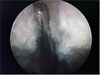

Zdjęcie regionu pod wyrostkiem barkowym (acromion) który jest widoczny u góry, poniżej wyrostka znajduje się kaletka maziowa (bursa subacromialis) tu bez zmian.

Zmiany prawego wyrostka barkowego z mocnym więzadłem kruczo-barkowym (lig. coracoacromialis), patrzymy od tyłu.

Wyrostek barkowy po tzw. dekompresji ( zwapnienie i przyczep więzadła kruczo-barkowego zostały usunięte).

Artroskopowa operacja stawu obojczykowo-barkowego przy zmianach artrotycznych : poszerzenie przestrzeni między obojczykiem i wyrostkiem barkowym.